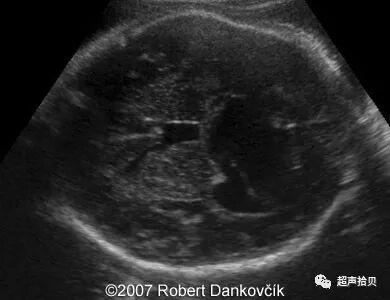

图2:冠状超声图显示位于后颅窝蛛网膜囊肿